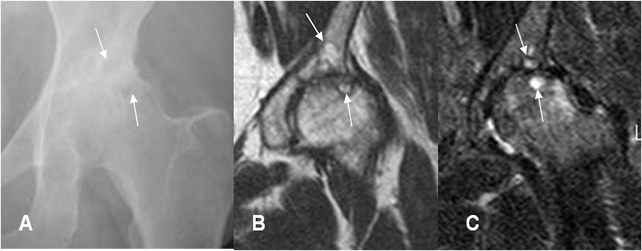

Fig 8. Artropatía degenerativa en cadera.

A: Rx AP de cadera. B: RM coronal en T2 y C: RM coronal en STIR. Pérdida del espacio articular, esclerosis y lesiones radiolúcidas en la Rx e hiperintensas en la RM, sobre la cabeza femoral y el acetábulo, que corresponden a quistes subcondrales. (Flechas).